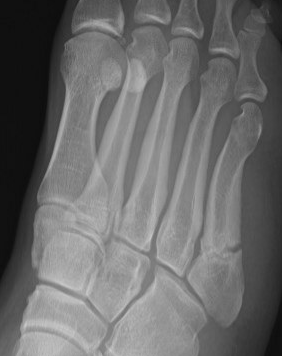

Xray

Zone 2 fractures

Union of zone 2 fracture with nonoperative care